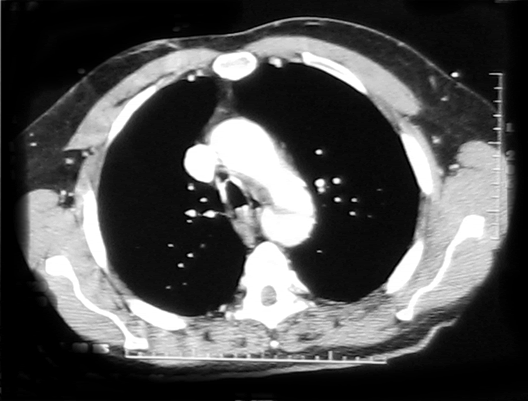

A 44 year old white male with 40 pack-year history of smoking was driving his motor cycle when a car struck him from the left side at approximately 40 mph. The patient lost consciousness at the scene, but upon arrival to trauma bay, he was alert and oriented. He complained of shortness of breath and pain in the left chest and left lower and upper extremity. The trauma team at the referring institution initiated advanced trauma life support pathway. He was found to have left femur, humerus, tibial-fibular and a complex pelvis fractures. The initial chest x-ray revealed a widened mediastinum (Figure 1), and a high-resolution contrast-enhanced computed tomography demonstrated proximal descending aortic rupture with hemomediastinum (Figure 2), left pulmonary contusion and a small left hemopneumothorax.